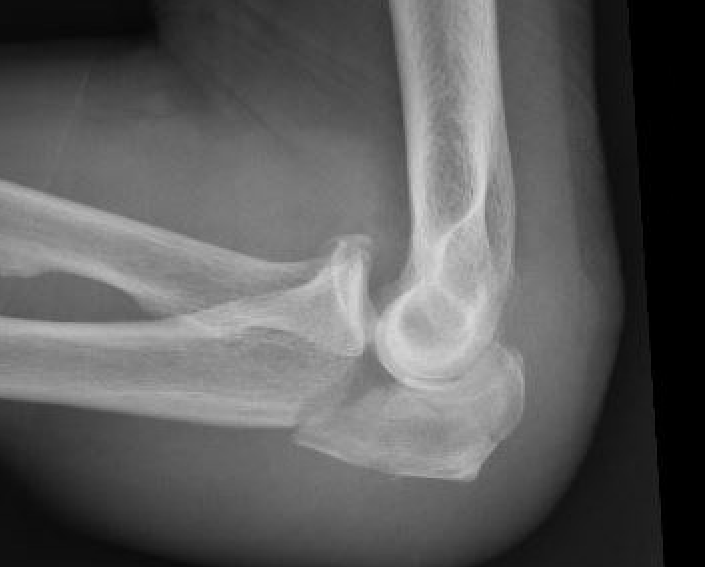

Complex proximal ulna fracture with radial head replacement subluxation